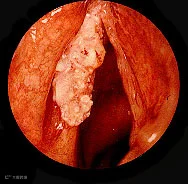

喉癌:患者常呈进行性加重的声嘶,喉痛,痰中带血,有时可引起呼吸困难。喉癌患者早期即可出现声音嘶哑症状,但因声嘶症状并不具有特异性,往往被患者忽视。